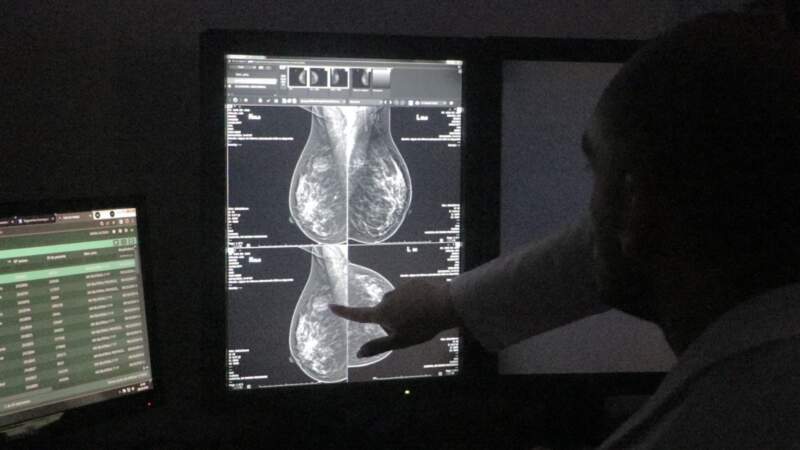

El Madariaga y sus unidades asociadas despliegan programas de screening como mamografías y controles ginecológicos, extendidos en toda la provincia gracias a redes articuladas con hospitales SAMIC y centros sanitarios.

El vínculo continuo con el paciente permite realizar seguimiento longitudinal y evaluaciones periódicas que mejoran los resultados de salud. La coordinación entre los servicios de diagnóstico temprano (como mamografía, PAP y campañas de tamizaje) con el tratamiento oncológico hace que el enfoque sea personalizado y centrado en el paciente.